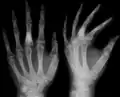

X-ray showing calcified enchondromas localized in finger a 37-year-old patient affected with Ollier disease

تتوضع الأورام الغضروفية بشكل حصري في العظام الطويلة وعظام اليدين والقدمين الصغيرة، ومن المهم التأكيد على التوزع غير المنتظم للآفات، فيمكن أن تكون في طرف واحد أو تقتصر على نصف جسم واحد، ومع ذلك حتى عندما تقتصر الأورام الغضروفية على جانب واحد من الجسم غالباً ما يوجد واحد أو اثنين من هذه الأورام على الجانب الآخر وخاصة في عظام اليد.